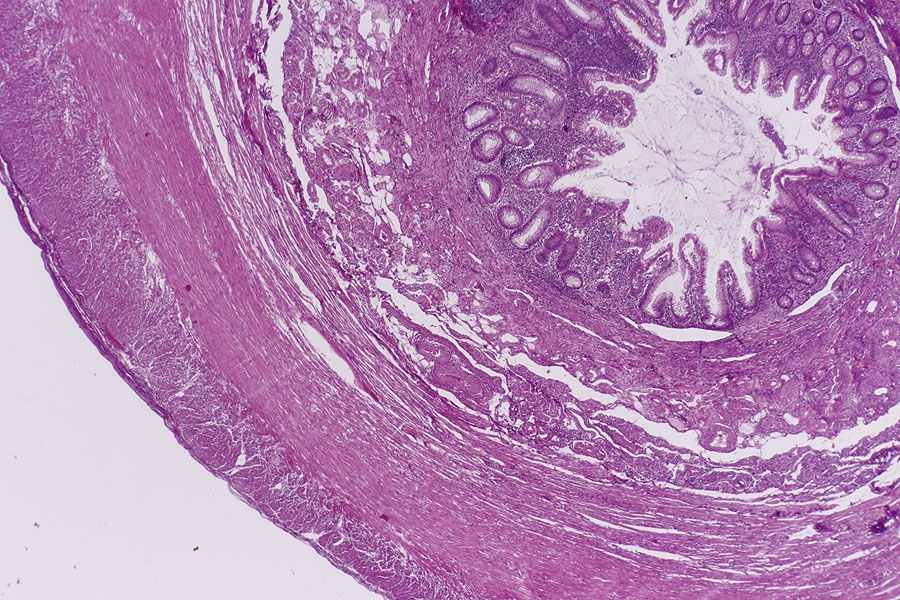

Im erste Blöckchen fand ich vom Aufbau einen typischen Appendix mit Mucosakrypten,

einer Submucosa mit Lymphfollikeln, einer inneren Ring- und einer äußeren Längsmuskelschicht so wie einem Mesenterialansatz. Was mich zuerst etwas irritiert hat war, das sich doch hier weniger Sekundärfollikel finden als ich es von anderen Präparaten gewohnt war. Das mag daran liegen, dass die meisten Appendixpräparate ja eine Appendizitis (Blinddarmentzündung) zeigen. Ronald Schulte hat das in einen tollen Beitrag im letzten Dezember beschrieben.

Ein zweites Präparat zeigt auch wieder den typischen Aufbau des Appendix und wenig gut abgrenzbare Sekundärfollikel.

Anfänglich war ich etwas irritiert durch zottenartige Bildungen der Schleimhaut, so wie eine sehr breite Submucosa. Doch sollten Zotten ja Blut-

und Lymphgefäße, so wie glatte Muskulatur enthalten die ich hier nicht gefunden habe, also sind es keine Zotten sondern nur Ausstülpungen

der Schleimhaut.

Übersicht